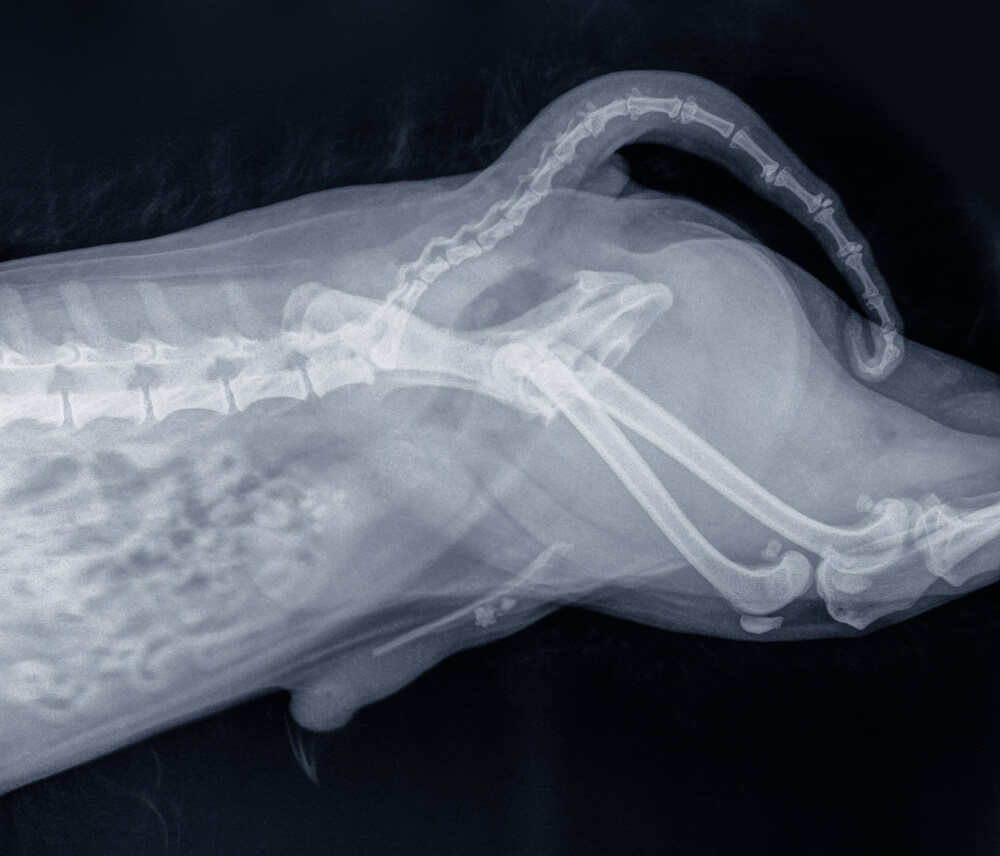

尿石症はどんな病気?

おしっこが作られてから体の外に出るまでの部位に石状のかたまりが出来てしまうことです。

・腎臓(おしっこを作るところ)

・膀胱(おしっこを貯めるところ)

・尿管・尿道(おしっこが流れるところ)

以上のどの部位にも出来る可能性があり、私たちヒトも犬も比較的多い病気といえます。

犬全般に起きる尿石症の多くはストルバイト結石とシュウ酸カルシウム結石です。

柴犬もこの2種類の発症に気をつけましょう。ほかは遺伝的な問題で犬種性が関わるものがあります。

見た目の様子ではわからなくても触診、尿検査、エコー、血液検査(腎臓の健康状態)等により診断ができます。定期的な健康診断も大事ですね。